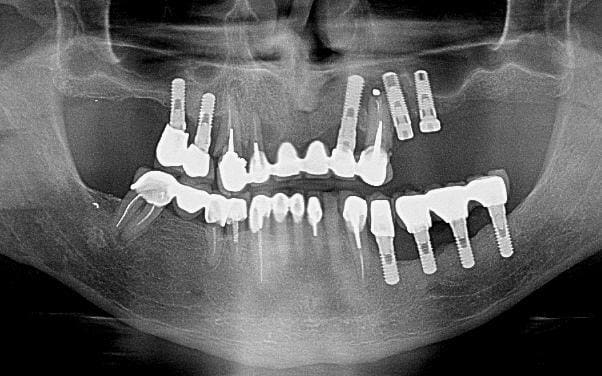

un cas un peu similaire. pilier naturel du bridge foutus. Implant IDI 15 14 22 posé en 2006 a boulogne, zimmer 24 25 en 2010 a la pitié-salpétrière. 14 mobile, foutu.

23 : grosse lésion avec fistule, visiblement au contact des implants 22 et 24.

Devenir de ces implants après l'extraction de 23 ?

Implant IDI, 35 36 37 en 2006, 34 en 2007, toujours a boulogne ( avec un chouette carnet implantaire, qui me donne toutes ces infos )

Toujours a propos du cas ci-dessus. Si la lesion guérit correctement et que les implants semblent ok : pour la suite : j'hésite entre 4 boules + complet sur o-ring ou dalbo, ( je pensais aussi a une barre, mais la distance entre l'implant 15 et 22 me semble trop grande) et faire des céram classique et stellite disjoint.

Dans le plan de traitement global, pour le haut il ne te reste que 4 implants si j'ai dien compris et le patient ne veut pas en rajouté, donc 3 à gauche 1 à droite,,, solution de compromis 4 locator sur prothèse complète amovible donc exo de la 23 nécessaire.

Hygiène et suivit faible pour ce patient... en 5 ans fonte osseuse importante au niveau des implants inférieur gauche.

Au point de vue mécanique la distribution des implants dans ce secteur était parfaite.